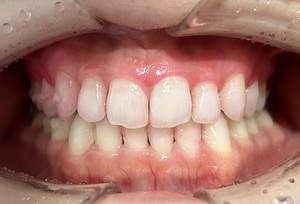

治療前

治療後

| 年齢 | 23歳・女性 |

|---|---|

| 主訴 | 着色取りたい |

| 治療内容 | エアフローで着色取り |

| 費用 | 5,500円(税込) (2024年07月現在) |

| 治療期間 | 1日 |

| リスク・副作用 | ナトリウムパウダーによるお口の不快感を伴うことがあります(うがいしていただくことで気にならない程度です)。 ケースにより完全に汚れを落としきれない場合があります。 歯ぐきの腫れや歯肉炎のある方は、ナトリウムパウダーがあたることにより、まれに痛みや出血をともなうことがあります。多くの場合、すぐに出血はおさまり、1~2日程度で歯ぐきは治癒していきます。 着色汚れはクリーニング後に再付着することがあります。定期的な受診をおすすめいたします。 |